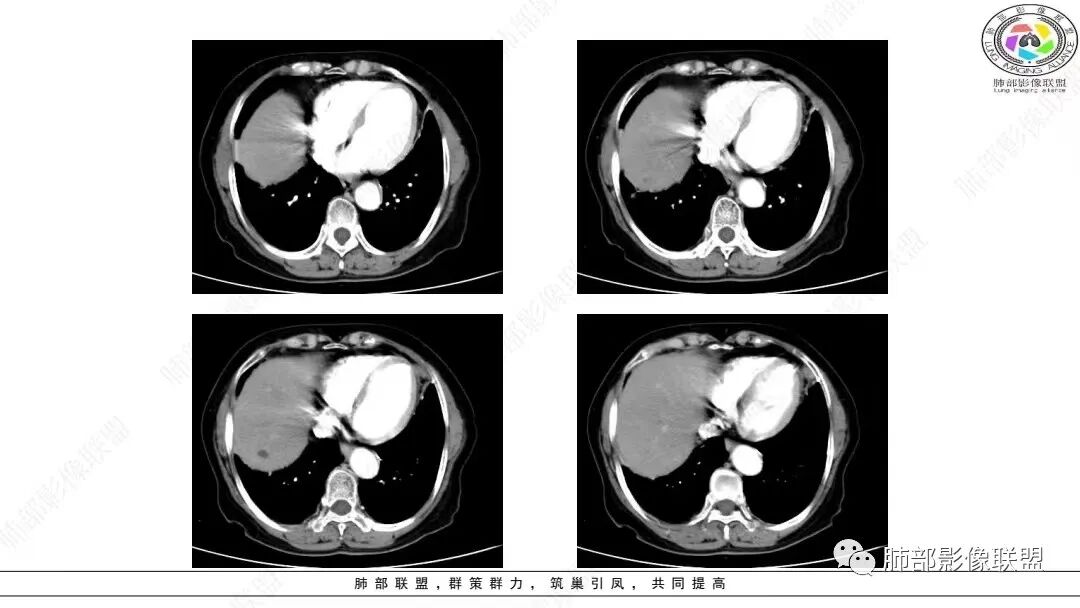

2.影像学特点:右肺上叶前段胸膜下不规则较大团块影,边界清楚欠光整,浅分叶,肺血管支气管出入,边缘膨隆胸膜凹陷具有一定张力,未见典型粗短毛刺,部分围以边界清楚的磨玻璃影,灶周小叶间隔增厚。块影密度不均,渐进性强化,可见砂砾样钙化,未见明显液化坏死或空洞。增强后病灶显示渐进性强化。MIP显示病灶内肺动脉穿行、并部分肺动脉受侵变细。纵隔及右锁骨上(胸廓入口)见肿大淋巴结。两肺可见多发大小不一的结节影,边界清楚,随机分布。

胸椎体溶骨性吸收破坏,突破骨皮质。腹部扫描未见肿块影。